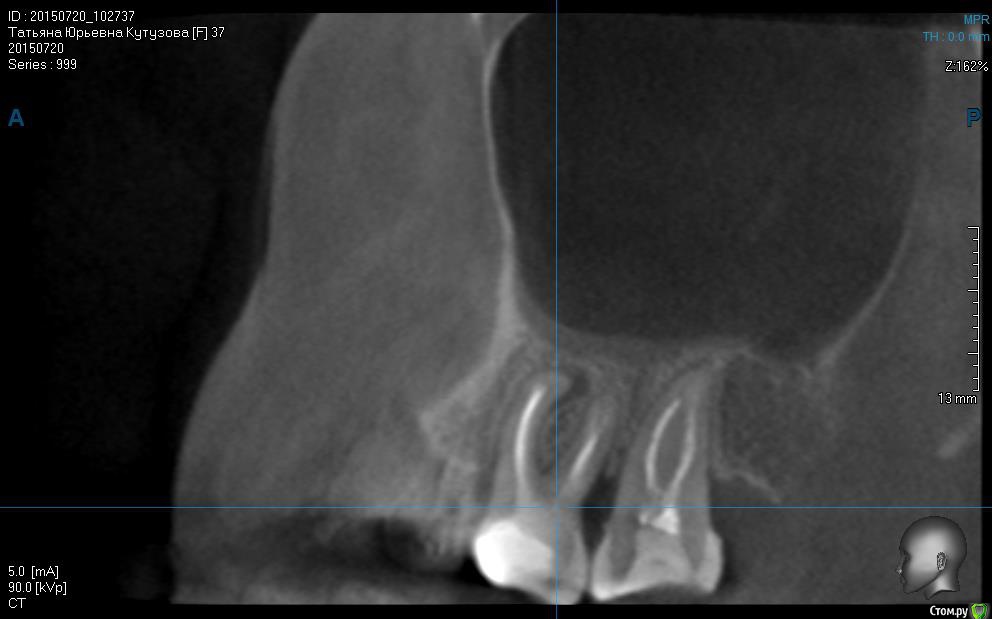

татьяна tat Опубликовано 16 декабря, 2015 Автор Поделиться Опубликовано 16 декабря, 2015 первый снимок после лечения,второй до! может кто нибудь сказать что то по этому поводу? Ссылка на комментарий

DmitrySH Опубликовано 16 декабря, 2015 Поделиться Опубликовано 16 декабря, 2015 Попытка лечения не принесла результата. Удалять. Ссылка на комментарий

татьяна tat Опубликовано 16 декабря, 2015 Автор Поделиться Опубликовано 16 декабря, 2015 Попытка лечения не принесла результата. Удалять.уважаемый доктор!!!!!!! скажите,умоляю....почему удалять? что с ним? боли у меня из-за него все таки?? Ссылка на комментарий

DmitrySH Опубликовано 16 декабря, 2015 Поделиться Опубликовано 16 декабря, 2015 Нет, я не могу знать откуда боли, от 6 зуба или нет .Но на данном зубе была и есть есть гранулема, зуб попытались вылечить, не вышло. Пытаться еще раз провести лечение - нет смысла. Ссылка на комментарий

татьяна tat Опубликовано 16 декабря, 2015 Автор Поделиться Опубликовано 16 декабря, 2015 Нет, я не могу знать откуда боли, от 6 зуба или нет .Но на данном зубе была и есть есть гранулема, зуб попытались вылечить, не вышло. Пытаться еще раз провести лечение - нет смысла.скажите пожалуйста....а мне кажется..или есть перфорация? Ссылка на комментарий

DmitrySH Опубликовано 16 декабря, 2015 Поделиться Опубликовано 16 декабря, 2015 Возможно, но вопрос в другом, канал не удалось полностью обработать. Ссылка на комментарий

Shaid Опубликовано 25 декабря, 2015 Поделиться Опубликовано 25 декабря, 2015 Постойте! Два последних снимка, что Вы скинули - с одинаковой датой. Контрольный снимок делается минимум через 6 месяцев, чтобы увидеть хоть какие-то положительные или отрицательные изменения. Ссылка на комментарий

татьяна tat Опубликовано 25 декабря, 2015 Автор Поделиться Опубликовано 25 декабря, 2015 (изменено) Постойте! Два последних снимка, что Вы скинули - с одинаковой датой. Контрольный снимок делается минимум через 6 месяцев, чтобы увидеть хоть какие-то положительные или отрицательные изменения.как это с одной??? вы что??? кт до перелечивания был сделан в июле....а после перелечивания в ноябрее....и как мне теперь постоять....если зуб мне удалили........ и чего было ждать,если DmitrySHсказал,что канал не удалось перелечить....и хирург на консультации сказал,что зуб на удаление...... Изменено 25 декабря, 2015 пользователем татьяна tat Ссылка на комментарий